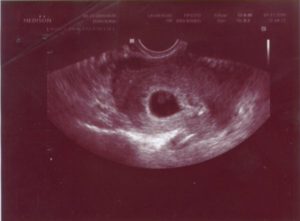

Четвёртая неделя беременности считается тем периодом, когда при помощи контроля УЗИ можно увидеть наличие эмбриона в полости матки. Средняя длина составляет около 5 мм. После 7 недели можно отчётливо увидеть зародыш, который имеет очертания головы, конечностей и тела.

Проведение ультразвуковой диагностики на данном сроке является важным показателем маточной беременности, так как следует исключить наличие внематочного оплодотворения яйцеклетки. Данная патология чревата плохими и иногда непоправимыми последствиями! Специалист также подтвердить правильное развитие эмбриона и отсутствие нежелательных диагнозов.